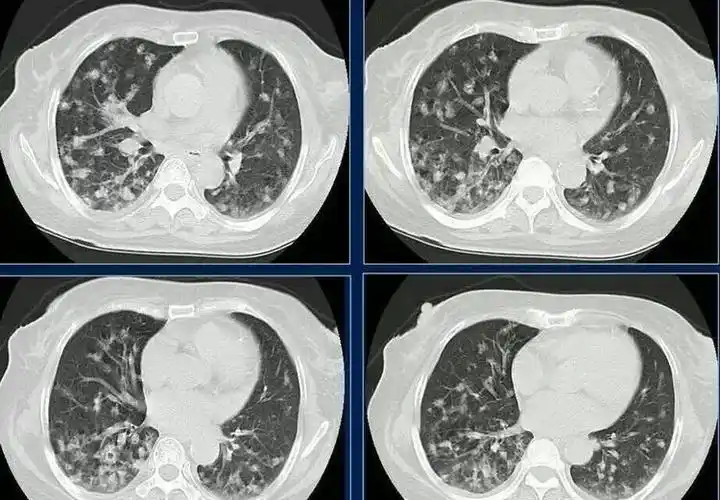

伴有粘液栓的肺结核 - 美篇